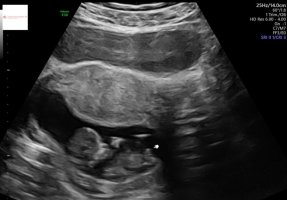

Jeg var på tidlig UL i dag, og da spurte hun først om vi var interessert i kjønn eller ville vente. Tror det varierer veldig fra sykehus til sykehus og de som jobber der. Vi fikk hvert fall vite at hun trodde det var jente, men kunne ikke si det helt sikkert - 13+0 i dag.Er det slik at de er skikkelig strenger på tidlig UL at de ikke ser på kjønnet?

Så jeg bestilte meg en privat UL, som jeg hadde tidligere i dag.